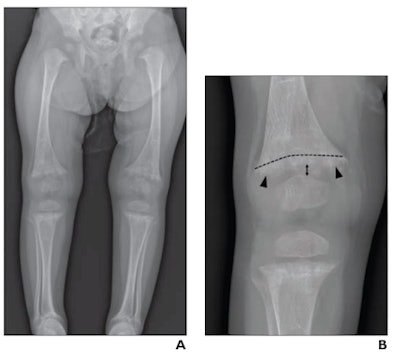

Thus, in this multicenter study, the researchers sought to address the issue by evaluating the diagnostic performance of radiologists in differentiating rickets and CML in children under 2 years old who underwent knee x-rays from January 2017 to December 2018. The children either had rickets (n = 70) or knee CMLs (n = 77) and a diagnosis of child abuse from a child abuse pediatrician.

Images were cropped and zoomed to present similar depictions of the knee, while eight radiologists independently interpreted the x-rays and rated their confidence levels for making diagnoses. Importantly, the radiologists were comprised of both pediatric and nonpediatric specialists with post-training experience ranging from one to 15 years.

According to the findings, the radiologists reached interpretations of rickets and CMLs with substantial to almost perfect agreement. For moderate- or high-confidence interpretations for CML, sensitivity across the eight radiologists was 95.1%, specificity was 97%, and accuracy was 96%.